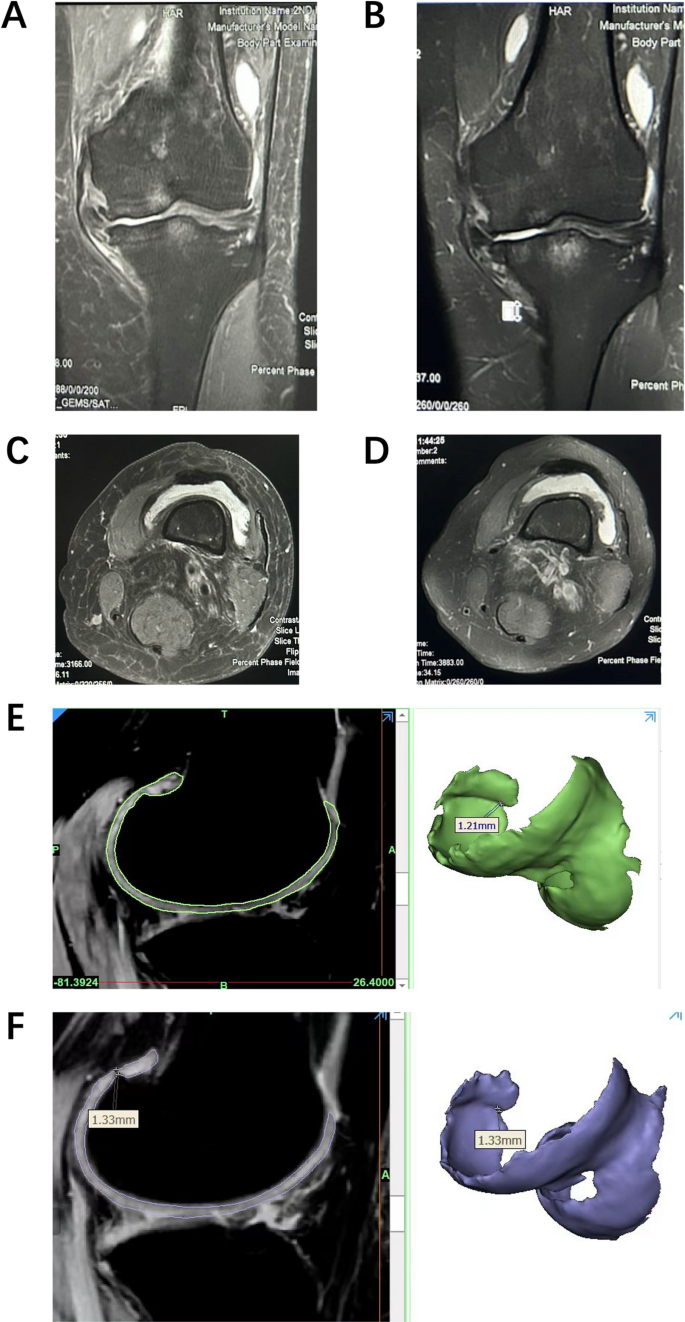

Before and after the injection of hUC-MSCs-Exos, MRI scans were performed for some patients, and imaging of cartilage tissue was extracted. It was observed that after the injection of Exos, the knee joint edema was significantly reduced, joint effusion decreased, and the level of knee joint inflammation showed clear improvement (Fig. 11: a\b\c\d). In the cartilage imaging, a certain degree of cartilage thickening was also detected (Fig. 11: e\f). These results indicate that exosome injection may help alleviate or even reverse the progression of OA, offering advantages over other traditional treatment options.

Knee joint MRI before and after hUC-MSCs-Exos injection: (a) Pre-injection knee MRI showing extensive bone marrow edema. (b) Nine months after injection, knee MRI shows reduced bone marrow edema area. (c) Pre-injection knee MRI showing a large volume of joint effusion. (d) Post-injection knee MRI showing a smaller volume of joint effusion. (e) Pre-injection knee MRI showing significant damage to the femoral cartilage. (f) Post-injection knee MRI showing thickened cartilage at the same location of the femoral condyle